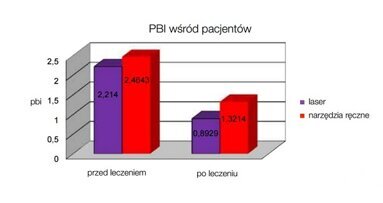

Laser Er: i Nd:YAG są obecnie narzędziem z wyboru w specjalistycznej terapii chorób przyzębia. Skutecznie redukują krwawienie (BoP) oraz głębokość kieszeni (Pd) w relatywnie krótszym czasie w porównaniu do konwencjonalnych metod leczenia. Inną zaletą jest większy dostęp światła lasera niż w przypadku narzędzi ręcznych, szczególnie w miejscach trudnodostępnych, jak np. głębokie wąskie kieszenie, furkacje czy bruzdy.